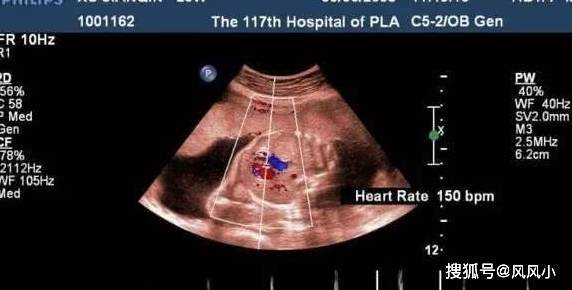

一般在3-4个月左右可以通过B超明确胎儿是男还是女,但是还要看胎位情况。胎位好看时就准确,不过也不要太过相信判断。

对于判断胎儿的性别来说,最直观的方法就是B超,B超下可以清晰的看清楚胎儿的各个器官和部位,包括生殖器。但是目前我们国家法律上规定,擅自告诉孕妇及家人胎儿的性别是属于违法的。